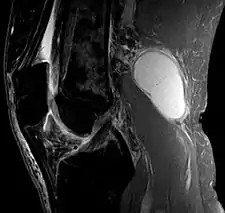

Baker's cyst on MRI, sagittal image